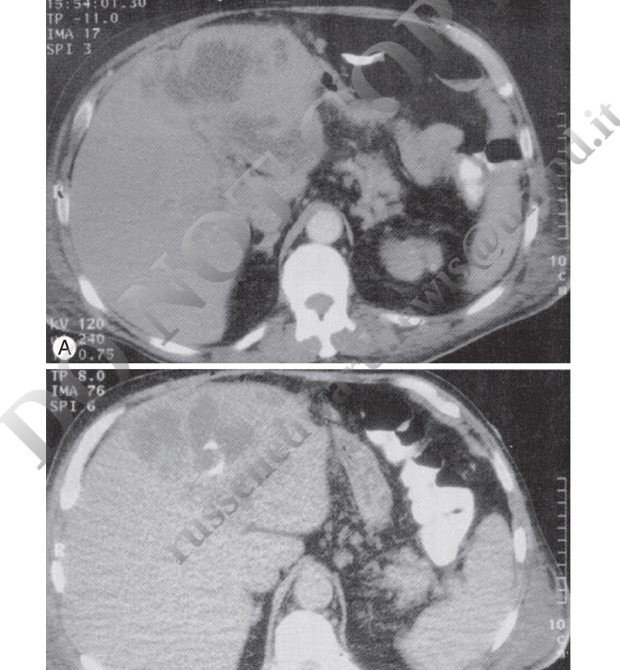

Figure 11: CT imaging of pyogenic liver abscess with percutaneous drainage. CT-guided aspiration is the preferred approach for both diagnostic confirmation and therapeutic drainage.

Figure 12: CT-guided drainage of liver abscesses. (A) CT revealing multiple hypodense lesions in the right hepatic lobe; (B) follow-up showing catheter in place and decrease in abscess size.